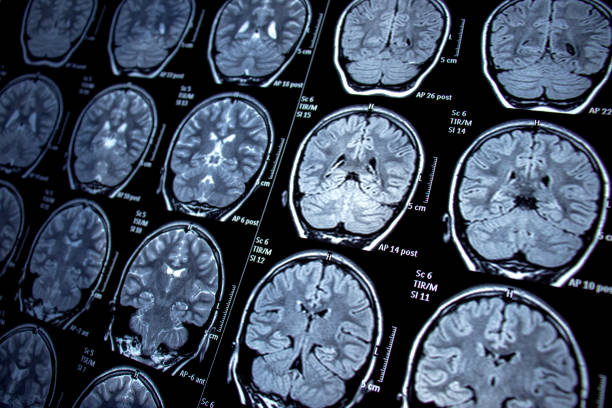

在出現(xiàn)兩例無誘因癲癇發(fā)作,或者一次在睡眠期間發(fā)作,或是發(fā)作時(shí)有心電圖(ECG)或磁共振成像(MRI)相關(guān)情況出現(xiàn)后,可考慮使用藥物。最佳做法通常是等待復(fù)發(fā)后再開啟治療,因?yàn)槭状伟d癇發(fā)作后馬上治療并不會(huì)改變預(yù)后情況。不過,對(duì)于發(fā)病風(fēng)險(xiǎn)較高的人群,像已確定存在結(jié)構(gòu)異常、腦電圖(EEG)異常或者已有神經(jīng)功能缺損的個(gè)人,則應(yīng)該盡早開始治療。

- 技術(shù)助力定位:隨著功能性磁共振成像(fMRI)等先進(jìn)成像技術(shù)的發(fā)展,外科醫(yī)生能夠定位癲癇區(qū)域,并確定大腦相應(yīng)區(qū)域手術(shù)可能導(dǎo)致的術(shù)后缺陷。

研究表明骨髓抽吸和隨后的細(xì)胞制備后,通過選擇性大腦后動(dòng)脈導(dǎo)管插入術(shù)將BMMC注入。對(duì)患者進(jìn)行6個(gè)月的隨訪。手術(shù)安全性、癲癇發(fā)作頻率、神經(jīng)心理學(xué)評(píng)估、EEG變量、常規(guī)腦磁共振成像和海馬體積測(cè)定被視為結(jié)果測(cè)量指標(biāo)。報(bào)告了與手術(shù)相關(guān)的任何嚴(yán)重并發(fā)臨床事件或不良反應(yīng)。未觀察到其他病變,也未觀察到顯著的海馬體積變化。